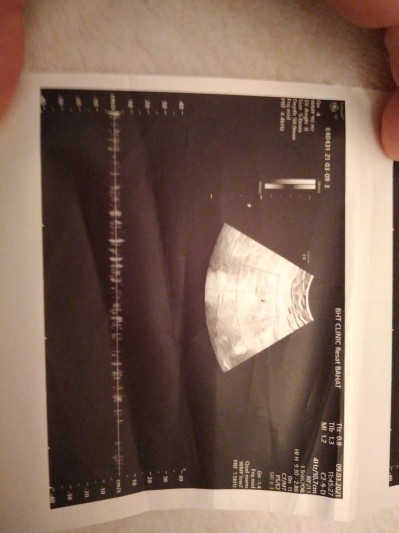

Usgde sizce kap atisinı gorebılıcekmıyım doktora gore 6 artı 5 ama kalp son adet tarihine gore 9 haftalık

Canım bak düz çizginin üstünde kalp atımı var aşşa yukarı çizgiler var eğer hiç kalp atışı olmasaydı o çıkmazdı. Sadece kalbi güçsüz atıyor oda küçük diyedir. Kaç mm kese boyu

Bunda yazmaz bu kalp atışı resmi. Normal resim çekmedi mi bı tane daha.

Canım o çizgiler kalp atışı bebeğin kalbi atıyor zaten sadece biraz zayıf ama o güçlenir inşallah duyarsın sende

Hıc atmıyo dedı 0da

Canım sen başka bi doktora daha git bebeğin kalbi dursa o çizgiler olmaz benim bebeğimin kalbi durdu kürtaj oldum çizgi falan yoktu ama bende

Bebegin kalp atisi var zaten

Çünkü var bebegin kalbi